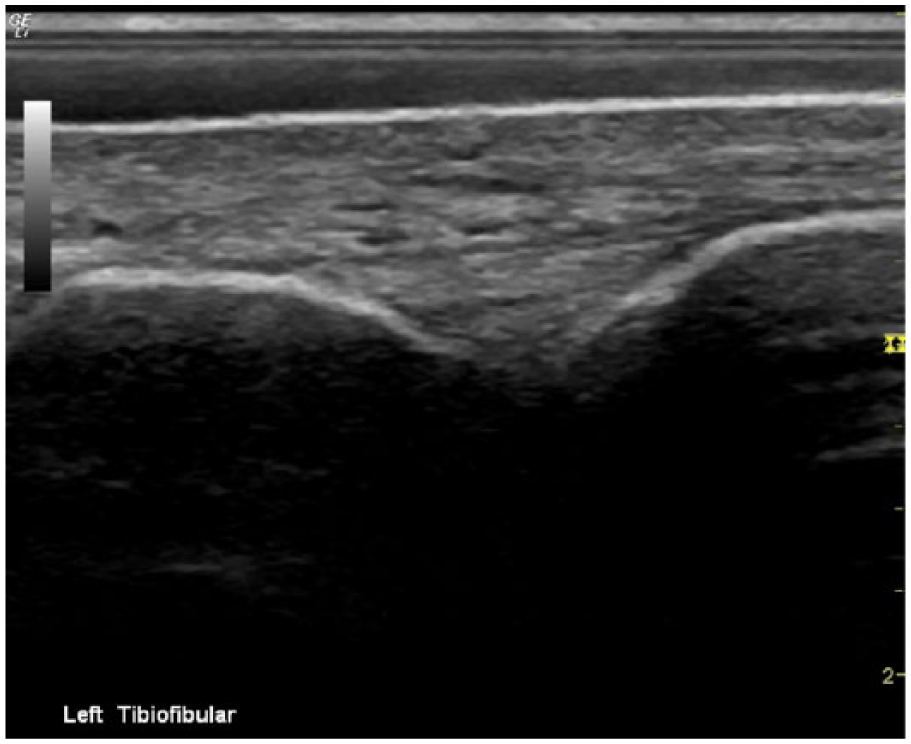

Long-axis sonogram showing a normal, asymptomatic left tibiofibular ligament.